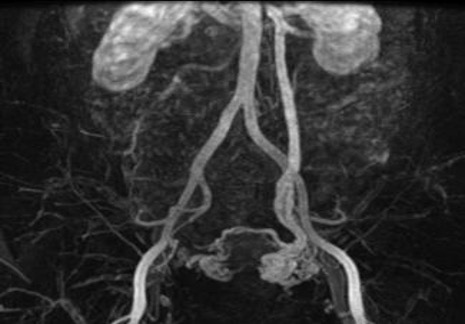

- Hỗ trợ chẩn đoán tốt hơn khi tìm thấy các nguyên nhân chèn ép, thấy vòng nối bàng hệ hai bên vắt qua phía trước hoặc sau tử cung trên CT, MRI.

- Chụp tĩnh mạch buồng trứng ngược dòng qua ống thông qua da (chụp tĩnh mạch buồng trứng ngược dòng) cho thấy các tĩnh mạch buồng trứng ngoằn ngoèo và giãn (đường kính trên 6 mm), trào ngược tĩnh mạch và tắc nghẽn đám rối tĩnh mạch buồng trứng, và thời gian rửa trôi của chất cản quang trong khung chậu cần hơn 20 giây. Hiện nay, chụp tĩnh mạch buồng trứng ngược dòng được coi là tiêu chuẩn vàng để chẩn đoán.